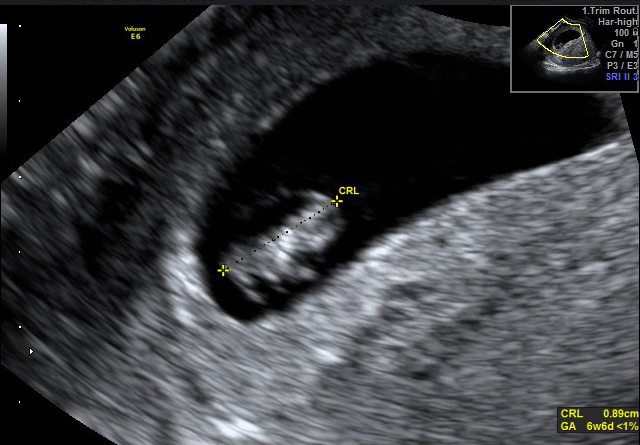

come una mamma aspetta quell’ecografia

spero che prenda da te ma con la testa mia”

Click dentro al pancione